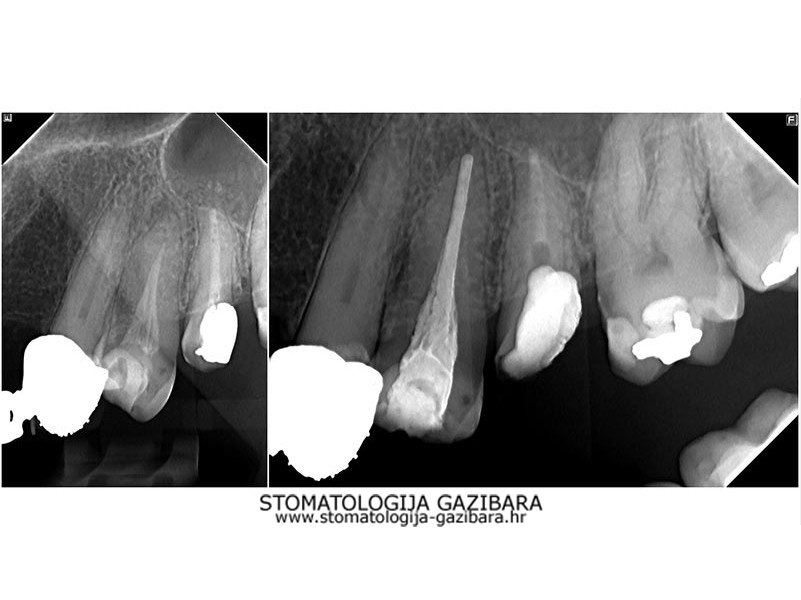

LIJEVO: 1a početno stanje,prednji zubi - DESNO: 1b nakon završetka terapijee LIJEVO: 2a revizija punjenja korijenskih kanala,višekorijenski zubi        <br />

DESNO: 2b nakon završetka terapije LIJEVO: 3a  prije revizije punjenja,jednokorijenski zub<br />

DESNO: 3b  nakon završetka terapije LIJEVO: 4a liječenje granuloma ,početno stanje<br />

SREDINA: 4b stanje nakon 9 mjeseci<br />

DESNO: 4c stanje nakon 3 godine, granuloma više nema !